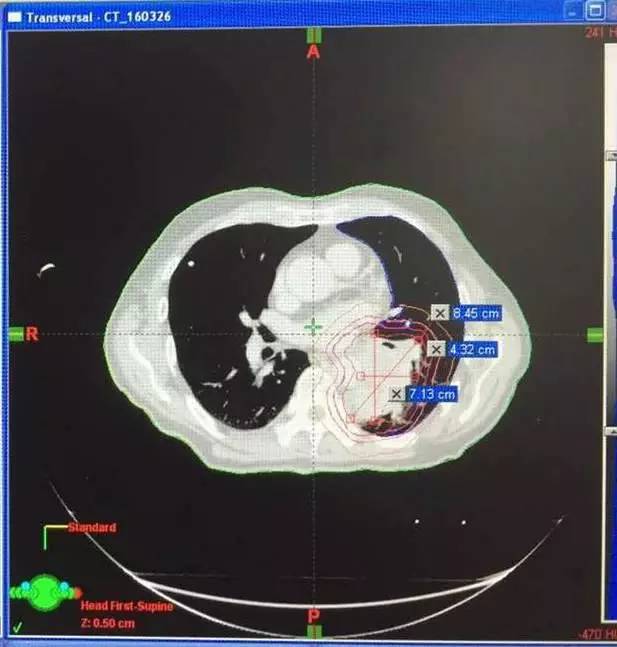

2、张女士,50岁体检时发现发现肺部结节,2016年5月,PET-CT诊断:右肺癌治疗后,双肺复发、右侧肾上腺多发转移灶,接受A45肿瘤治疗复查结果显示肺上三个病灶消退。

左图红色圈内是A45治疗前三个肺癌病灶,右图为治疗后病灶消失